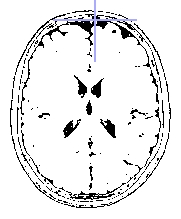

Threshold + Binary mode : selected voxels are white and the others are black